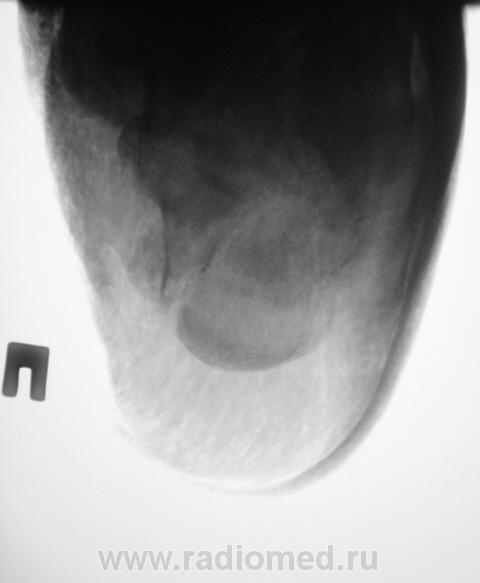

Лечение состояло из "множества рентгенов" и гипса. Срок - 5 месяцев.

Сейчас думают об остеомиелите.

Контуры пяточной кости относительно четкие, разрежение структуры пяточного бугра, в проекции перелома уплотнение структуры кости( имею в виду последние снимки).Клиника остеомиелита есть?

Клиники остеомиелита, с моей точки зрения, нет.

А что Вы в протоколе написали?Я тоже не вижу остеомиелита.

Во-первых, деформация пяточной кости; во-вторых, отсутствие консолидации, через некоторое время и ложный сустав сформируется. Неоднородное уплотнение костной структуры в теле кости может быть обусловдено как остеомиелитом, так и перераспределением нагрузки.

Признаков остеомиелита не вижу, только консолидир перелом с неуд стоянием отломков.